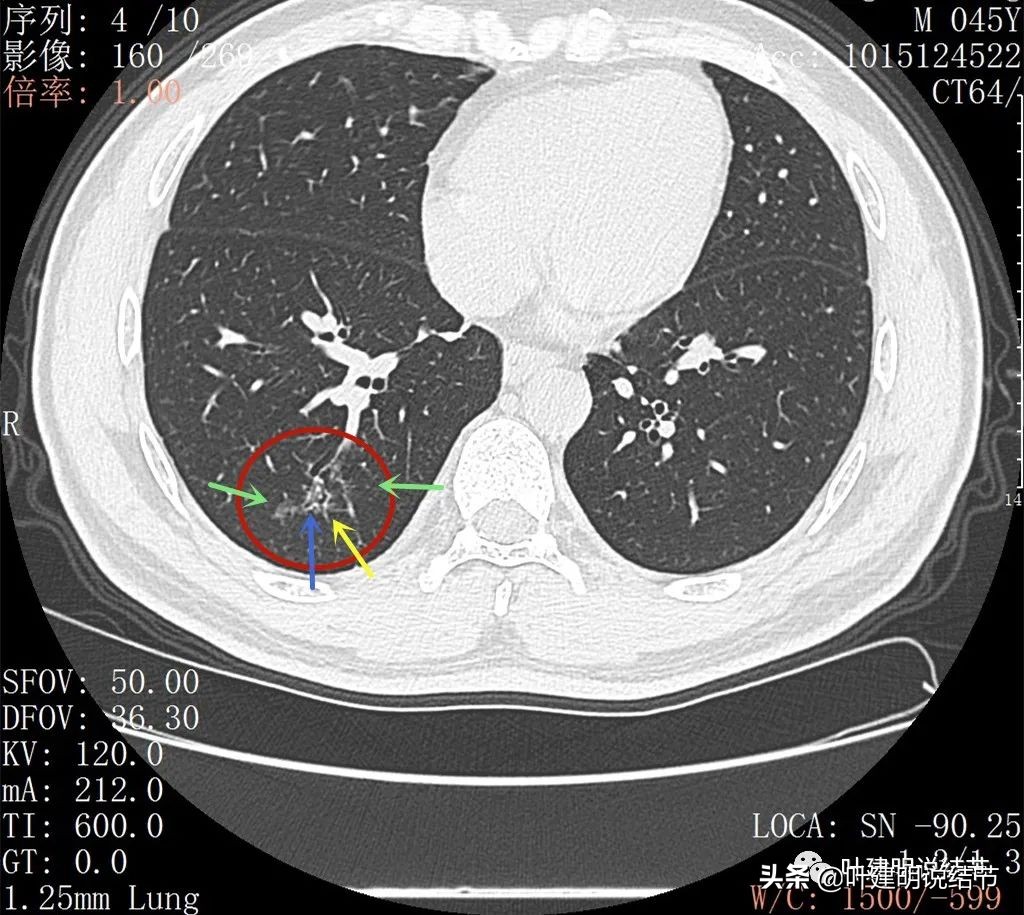

2022年2月平扫:

右下叶淡而散在的磨玻璃影

整体轮廓有点清楚,似见血管走行于病灶处

密度略不均

再来看薄层扫描:

病灶感觉很散在,但内部有扩张的细支气管(黄色箭头)、边缘略显不清(绿色箭头),部分有偏实性(粉色箭头)。

边缘血管异常增粗(桔色箭头),边缘显糊(绿色箭头),细支气管扩张(黄色箭头)

病灶似乎非圆形或类圆形,扩张的细支气管壁密度偏高(蓝色箭头),感觉比较僵硬(黄色箭头),病灶轮廓显模糊(黄色箭头)

扩张细支气管壁密度较高,病灶轮廓显糊